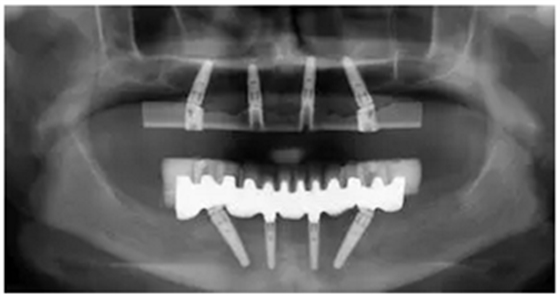

手術(shù)后16周最終修復(fù)X光片:計算機輔助導(dǎo)板引導(dǎo)種植能夠保證在All-on-4治療中精準(zhǔn)安全地植入軸向和傾斜植體。